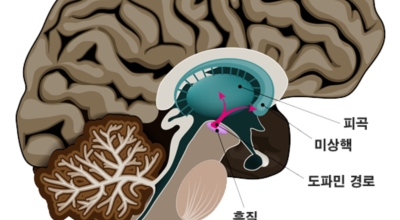

파킨슨병은 도파민 분비 신경 세포의 소실로 발생하는 질환으로 알려져 있는데요 도파민이란 뇌의 신경세포에서 만들어지는 물질로 세포와 세포 간의 신호를 전달하는데 이용되는 신경 전달 물질 중 1개로 이 도파민이 감소함에 따라 파킨슨병이 걸린다고 하는데 이 도파민 세포가 떨어지는 이유는 아직 정확히 알려지지 않았다고 합니다. 일부 파킨슨 환자는 파킨슨병의 가족력이 있는 경우가 있으며 이런 가족들 중 일부에서는 유전자 이상이 발견되기도 해요.